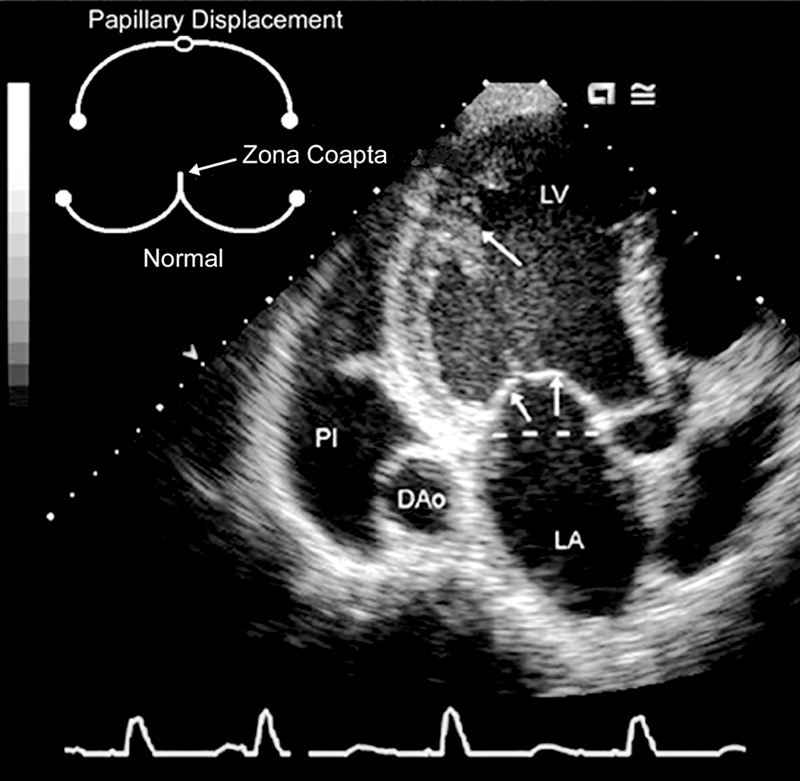

فحوصات تشخيصية لبعض امراض القلب والشرايين التاجية